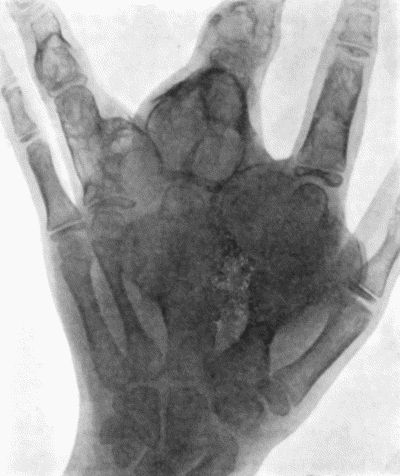

| 142. | Multiple Chondromas of Phalanges and Metacarpals | 488 |

| 143. | Skiagram of Multiple Chondromas | 489 |

| 144. | Multiple Chondromas in Hand | 490 |